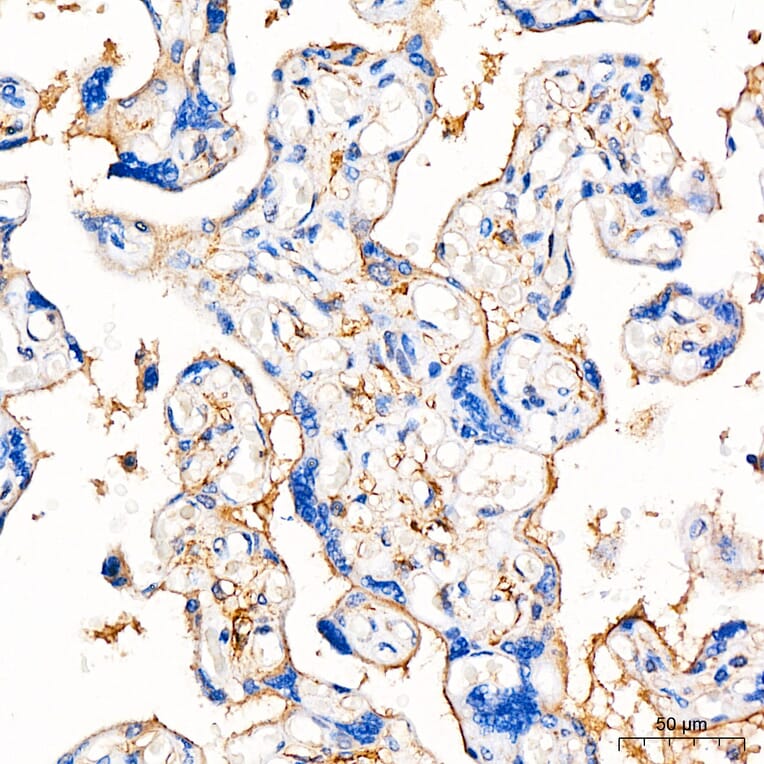

B7-H3 expression in human placenta tissue analyzed by immunohistochemistry. Tissue was paraffin-embedded, and antigen retrieval was achieved with 10 mM citrate buffer, pH 6.0, under high pressure. Staining was performed with Anti-B7-H3 Antibody (A329142) at a dilution of 1:200.